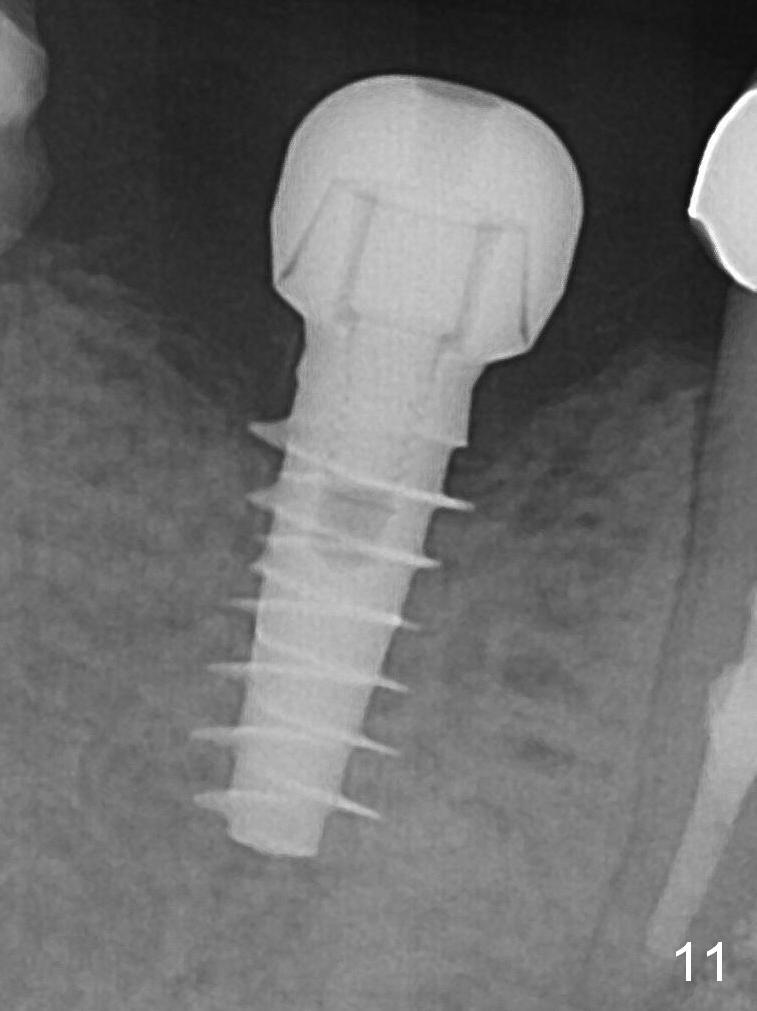

Splinted provisional is fabricated #30 and 31 one month postop.  The patient returns for final restoration (single units) nearly 4 months postop (Fig.11).  Since the margin is subgingival, please fabricate a screw type crown for #30.